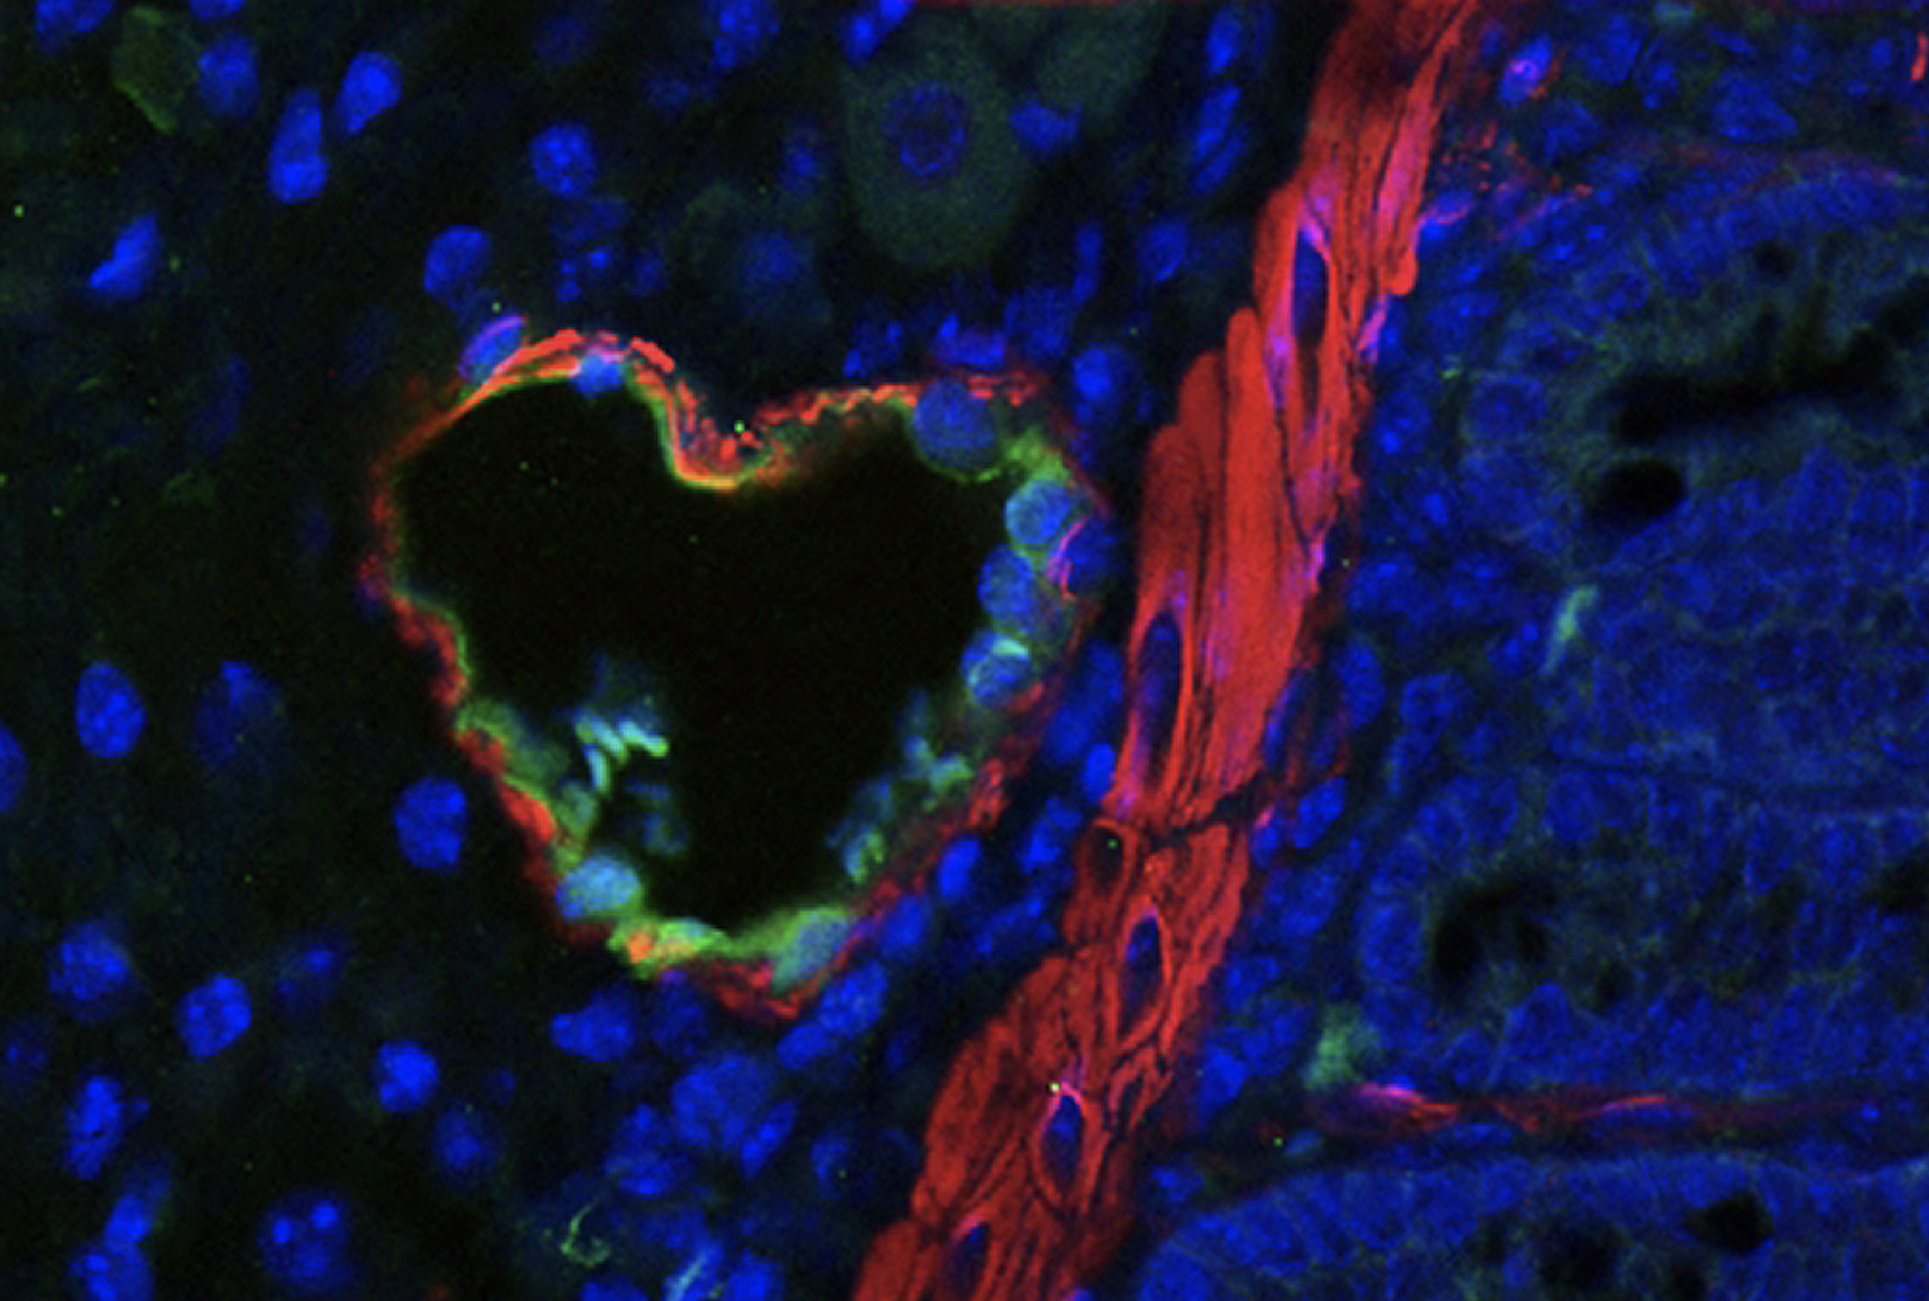

Au cœur des vaisseaux

Ce tableau aux accents psychédéliques n’est pas l’œuvre d’un artiste contemporain de renom. Il s’agit de l’observation au microscope – grossissement x400 – d’une section de rectum de souris préalablement irradié. Chaque couleur, obtenue par marquage fluorescent, correspond à une structure biologique particulière : rouge pour le mésenchyme et la paroi des vaisseaux sanguins, vert pour leur endothélium et bleu pour les noyaux des différentes cellules de l’échantillon tissulaire.